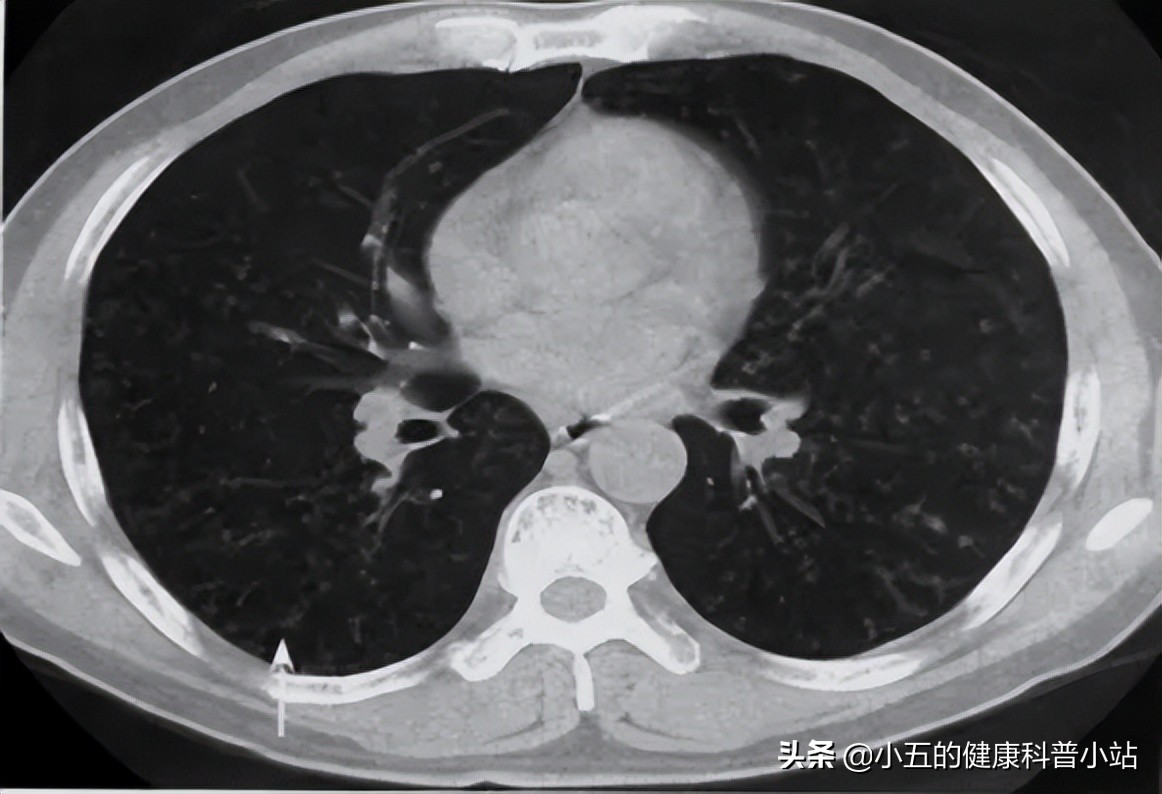

2周前武汉这边的天气突然降温,王大爷咳嗽咳痰的*毛老**病又犯了,但是程度不太重,所以也就没当回事, 结果咳痰越来越多,颜色也由白转黄,而且伴有明显的喘息和胸闷,甚至晚上睡觉都可以咳醒 ,家里人连忙将他送到医院急诊进行治疗。 医生通过肺部CT检查发现王大爷患有大叶性肺炎,并且有着严重的慢性支气管炎 ,于是将其收治入院,经过抗感染、化痰、止咳、平喘等对症治疗后王大爷的症状明显好转了。

许多细菌感染导致的呼吸道疾病都会表现出咳嗽咳痰, 其中大叶性肺炎、间质性肺炎等多以咳粘痰、浓痰等为主,而且往往难以咳出 ,而乙 酰半胱氨酸泡腾片可以有效分解粘痰、浓痰,将其稀释后更容易从呼吸道中排出 ,因此常与抗感染药、扩张支气管药等联用,有利于快速控制感染病情,改善患者临床症状。